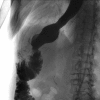

Endoscopic closure of a refractory enterocutaneous fistula by use of a fistula plug with fixation and mucosal oversewing